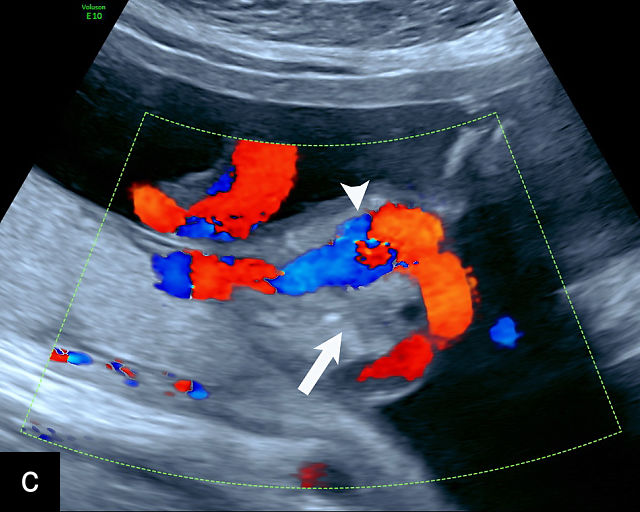

Ultrasound is the primary diagnostic method for identifying VCI. Normally, the cord inserts into the center or edge of the placenta and is fully protected by Wharton’s jelly. In contrast, a velamentous cord insertion is visualized on ultrasound as the cord inserting into the membranes, with unprotected fetal vessels running to the placental margin (Figure 20; Video 11). Color flow Doppler and three-dimensional ultrasound can enhance diagnostic accuracy. Velamentous cord insertion may also occur into the dividing membrane in a multifetal pregnancy (Figure 20e). When unprotected fetal vessels from a VCI cross over the cervix, the condition is termed vasa previa, posing a significant risk of fetal exsanguination if these vessels rupture. Because VCI is a strong risk factor for vasa previa, a color flow Doppler sweep over the cervix is recommended when VCI is identified. If concerns about vasa previa persist, transvaginal ultrasound with color Doppler may be performed for confirmation.30

20

(a–c) Grayscale (a) and color Doppler (b,c) ultrasound images of velamentous cord insertion. The cord inserts into the membranes (arrow), from where unprotected fetal vessels (arrowheads) traverse the membranes to insert into the edge of the anterior (a,b) or posterior (c) placenta (p). (d) Color Doppler ultrasound image of velamentous cord insertion, showing the cord inserting into the membranes posteriorly (arrow), from where unprotected fetal vessels (arrowheads) traverse the membranes to insert into the edge of the anterior placenta (p). (e) Ultrasound with color Doppler showing velamentous vessels (arrow) running through the dividing membrane in a dichorionic diamniotic twin pregnancy. The right image shows the placenta after delivery.